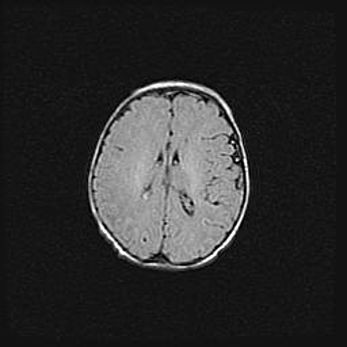

Сообщающаяся гидроцефалия. Кистозная энцефаломаляция головного мозга.

Возраст: 3 месяца 4 дня

Вес: 3100 г

Пол: женский

Окружность головы: 34 см

Срок гестации: 31 неделя

Кистозная энцефаломаляция головного мозга - одна из форм поражения головного мозга в детском возрасте. Характеризуется возникновением множественных и распространённых кист в коре, белом веществе и подкорковых образованиях головного мозга у плодов, новорождённых и детей раннего возраста. Развитие кистозной энцефаломаляции связано с внутриутробной асфиксией и гипотонией, родовой травмой, тромбозом синусов, пороками развития сосудов, инфекциями, сепсисом и другими причинами. Наиболее значимые инфекционные агенты: вирусы простого герпеса, цитомегалии, краснухи, токсоплазмы, энтеробактерии, золотистый стафилококк и другие.